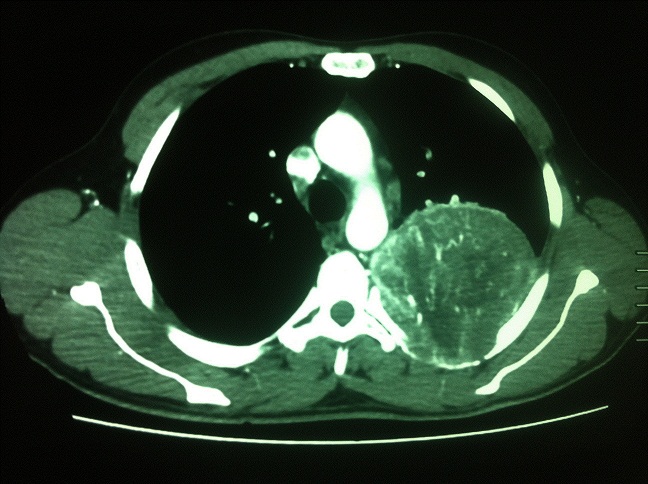

Un patient âgé de 48 ans, tabagique et cannabique chronique, a consulté pour une toux sèche associée à une douleur thoracique sous mammaire gauche qui persistait depuis 3 mois, dans un contexte de conservation de l'état général. L'examen à l'admission retrouvait une matité du tiers supérieur de l'hémithorax gauche. Le scanner thoracique avec injection a objectivé une grosse masse pulmonaire apico-dorsale gauche arrondie bien limitée, mesurant 94x77x83 millimètres, renfermant des calcifications fortement rehaussées après injection de produit de contraste et arrivant au contact de l'aorte descendante avec un liseré graisseux de séparation. La bronchoscopie a montré un état inflammatoire du premier degré diffus, sans tumeur visible. Le bilan d'extension était négatif. Le patient a été opéré par thoracotomie postéro-latérale droite. L'exploration chirurgicale a objectivé une masse tumorale au dépend de la plèvre pariétale de 15 cm de diamètre, ovalaire, prenant tout l'apex, adhérente au lobe supérieur droit et au lobe inférieur et laissant le parenchyme pulmonaire intact. Une résection complète de la masse a été réalisée avec bonne évolution en postopératoire. L'examen anatomopathologique de la pièce opératoire a conclu à une tumeur fibreuse solitaire avec une forte expression de l'anticorps anti-CD34. L'évolution a été bonne après un recul de deux mois.